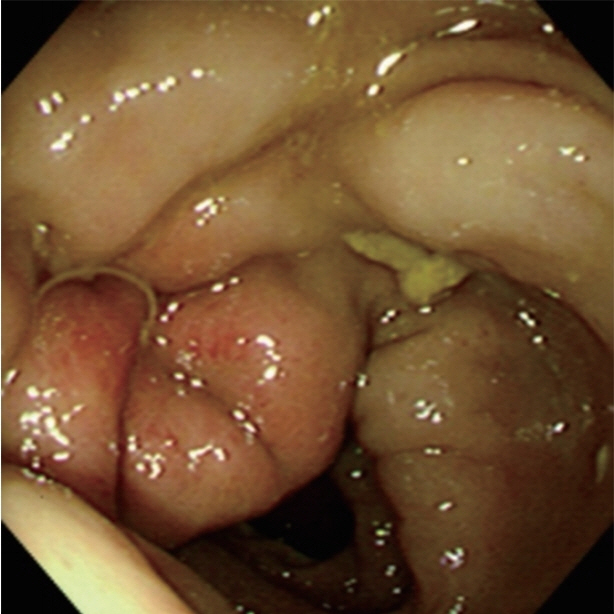

Larval Anisakis are grossly visible, measuring approximately 2–2.5×0.1–0.2 cm. In colonic anisakiasis, colonoscopic findings show hyperemic and edematous mucosal changes due to colonic wall invasion by the larvae (Fig. 1). Regardless, morphologic proof of an Anisakis larva in the resected specimen is the best basis for a diagnosis [26]. In histological sections, Anisakis larvae have distinctive Y-shaped lateral cords, 60–90 muscle cells per quadrant, and no lateral alae or wing-like projections extending from the cuticle, similar to Ascaris larvae [1].

Fig. 1

Colonoscopic findings of anisakiasis in case no. 12.

Fig. 1 Colonoscopic findings of anisakiasis in case no. 12.